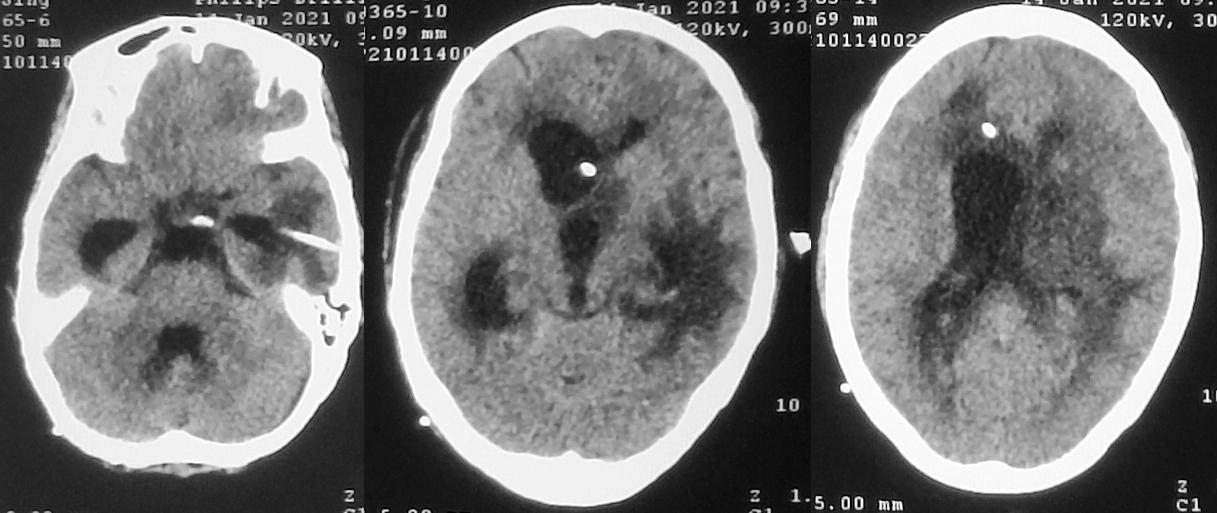

患者于2020年11月8日无明显诱因出现间断头痛。发病5天后,即2020年11月13日到当地的河南省潢川县某医院行头颅CT检查( 图-1 )发现左侧丘脑病变。

图-1: 2020年11月13日头CT

入院当天,患者出现恶心、呕吐数次,意识变差呈昏睡状态,强刺激才能睁眼。复查头颅CT见左侧丘脑病变增大,周围水肿明显,脑室扩张( 图-3 ),医生给予脑室穿刺外引流术。

图-3: 2020年11月21日头CT

脑室外引流术后第2天即2020年11月22日早上8点,患者好转为清醒,复查头颅CT见左侧脑室缩小( 图-4 );但患者出现发热,引流出的脑脊液浑浊,医生考虑患者丘脑病变为脑脓肿,给予头孢曲松抗炎治疗。

图-4: 2020年11月22日头CT

但当天晚上21:00,意识再次变差为嗜睡,复查头颅CT见脑室扩张( 图-5 ),考虑脑室引流不通畅,给予调整引流管后引流好转。

图-5: 2020年11月22日晚上头CT